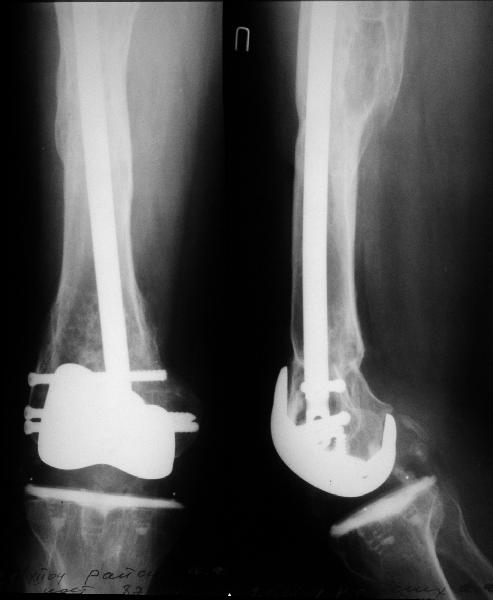

Go antegrade if you have an approriate implant available. Attached is a result of a similar fracture.